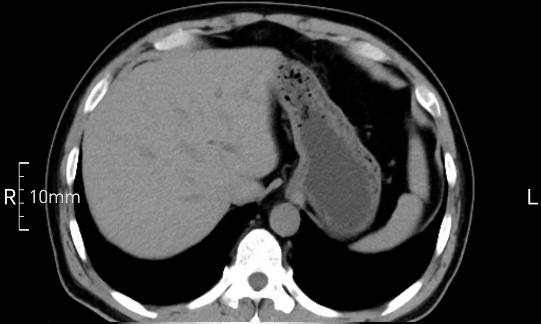

看看下面三幅便知遵醫囑的重要性。

禁食但檢查前沒有喝飽,胃未能漲開,胃壁觀察效果不佳。